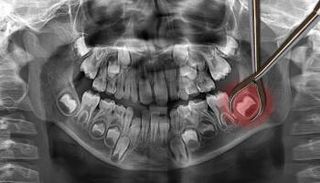

مكنت تقنية الطباعة ثلاثية الأبعاد الأطباء في الولايات المتحدة من إعادة بناء فك مريض بعد إزالته بسبب ورم سابق.